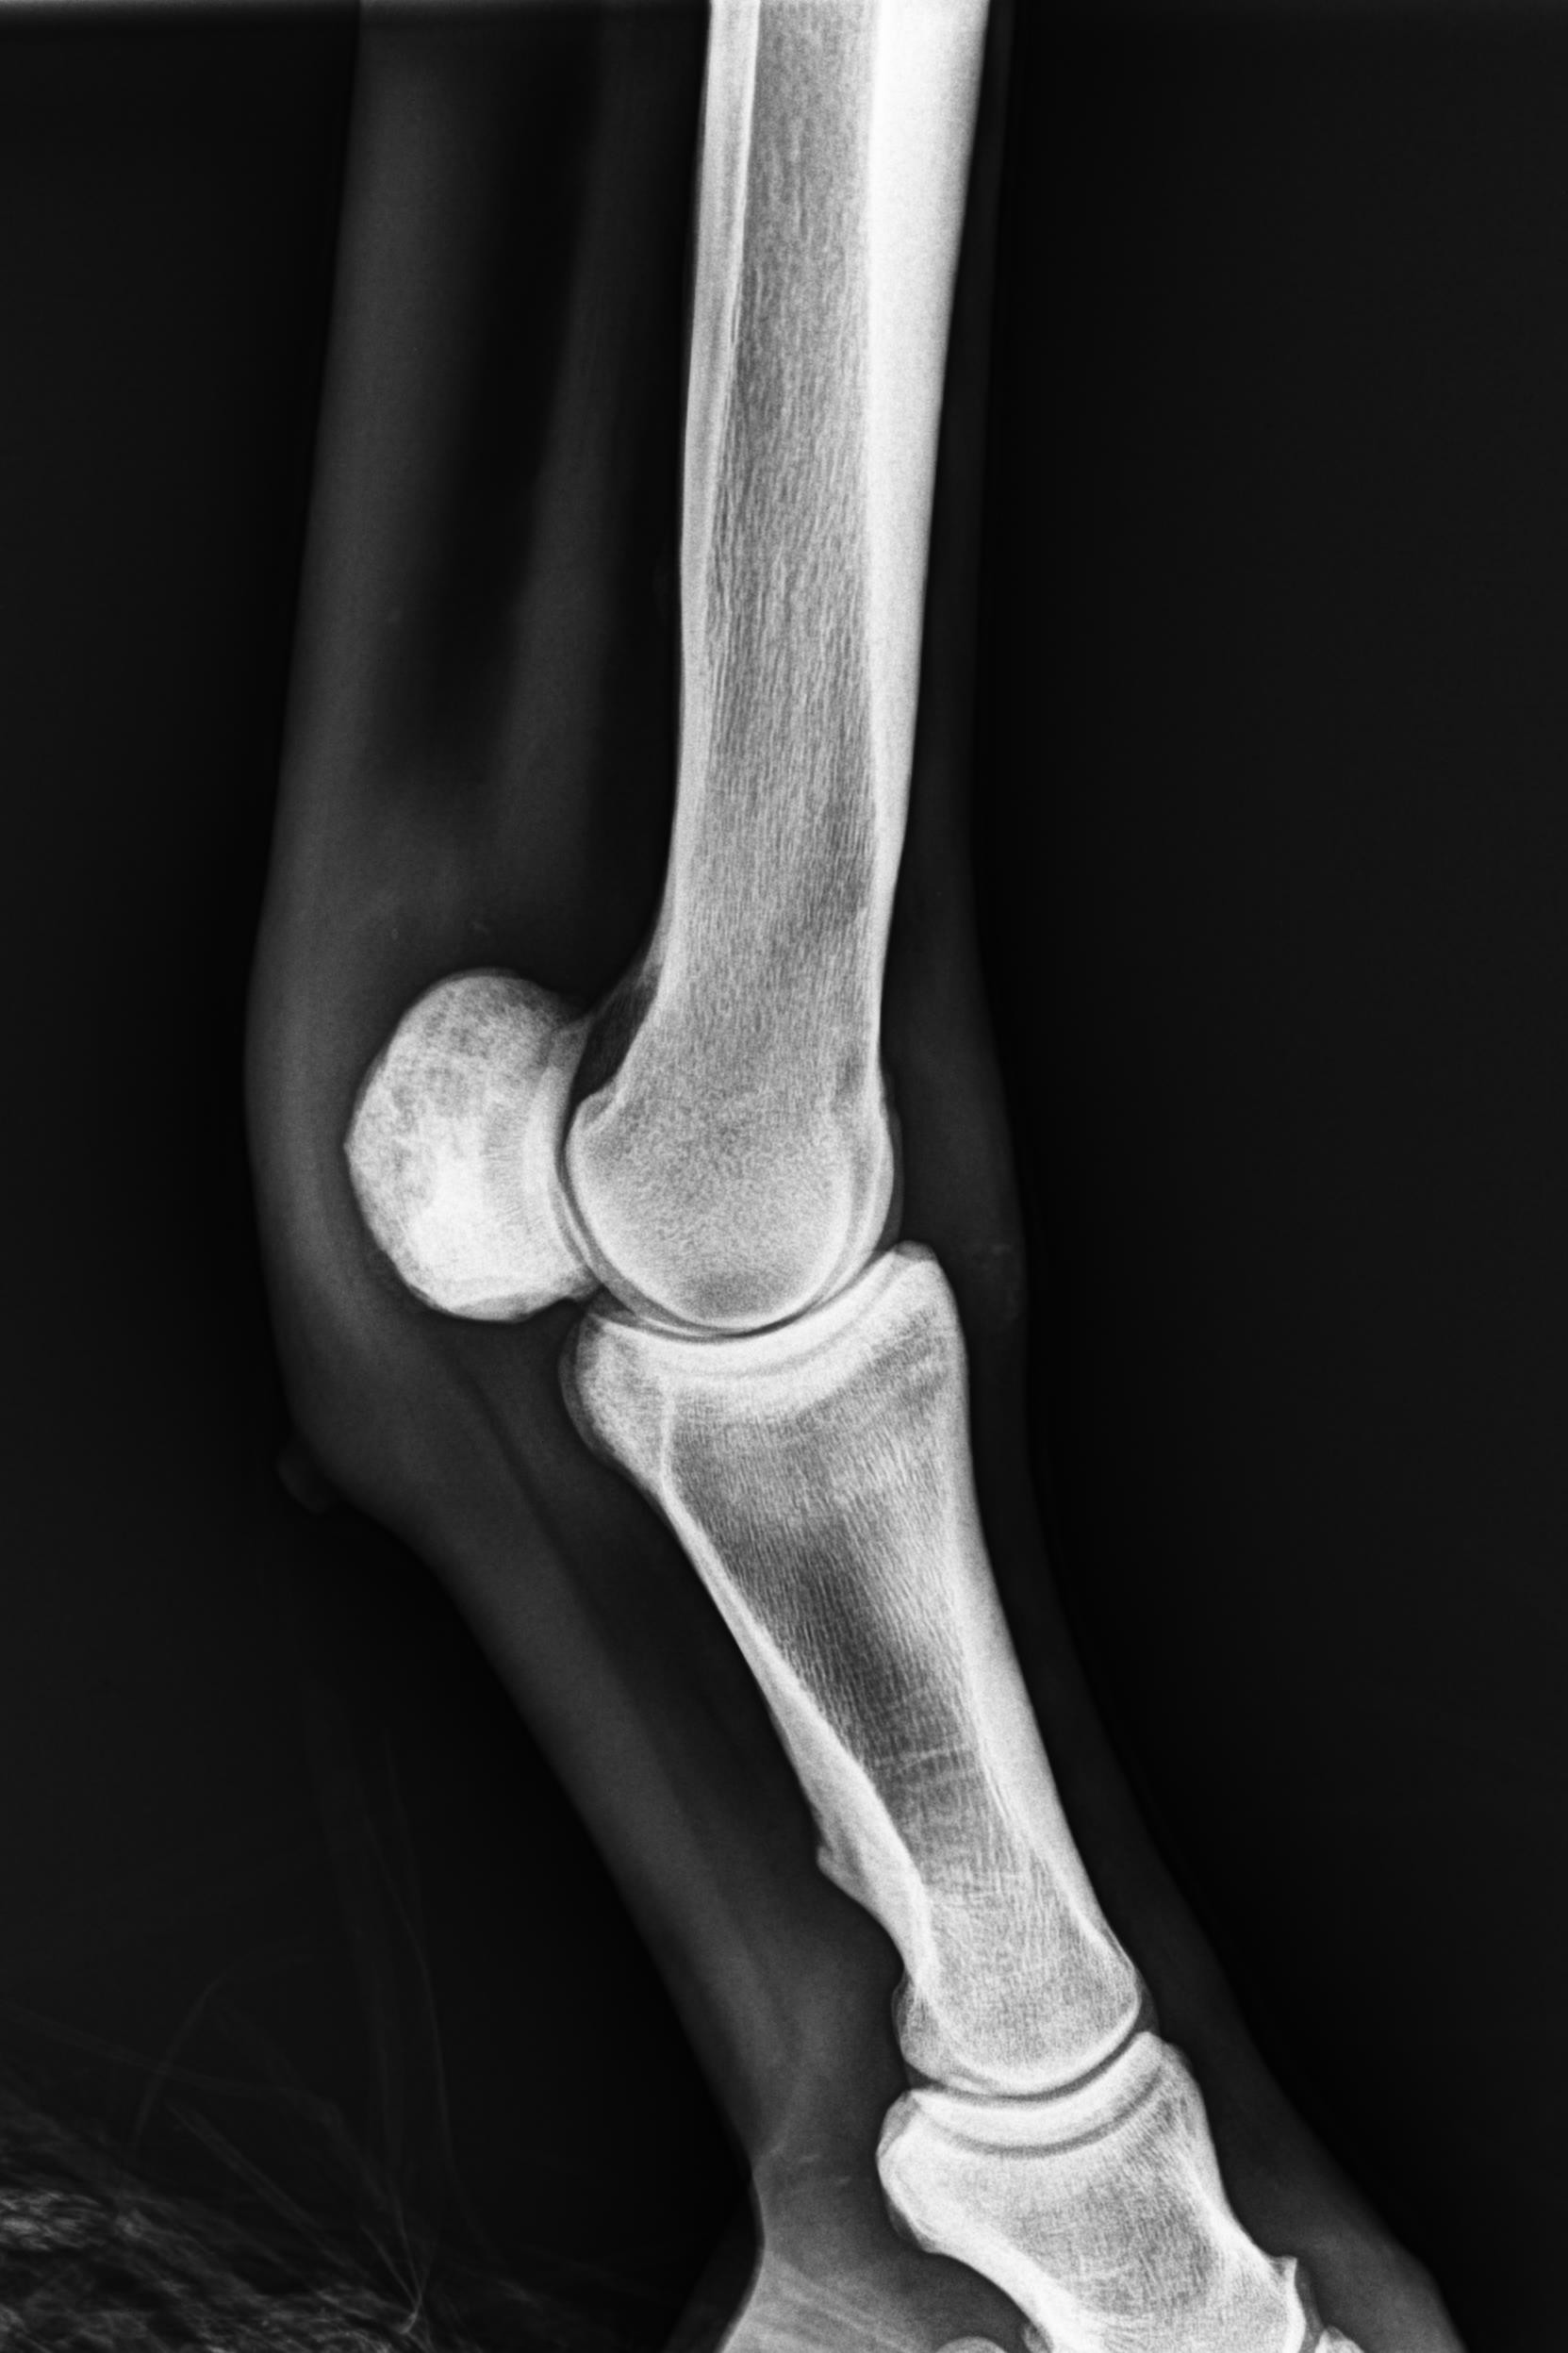

そんな状況の中、1月9日にレントゲン検査を受けると「左前肢外側の種子骨のボーンシスト」が原因と判明しましたので、サラブレッドオークションへ出品とさせていただきます。現状のままでは競走馬としてのデビューは難しいかも知れません。皆様には現状をご理解いただき、事前に獣医検査を受ける等、ご納得をいただいた上でのご検討、ご入札をお願いし、現状渡しのノークレーム、ノーリターンでお願いいたします。

セールの後からお預かりして来ましたが、レントゲン検査を受けて獣医から「このまま調教を進めたら骨折するリスクが大きい」との所見でした。競走馬は勿論ですが、現状のままでは乗馬としても厳しいと思います。(Team百馬力・原翼氏)